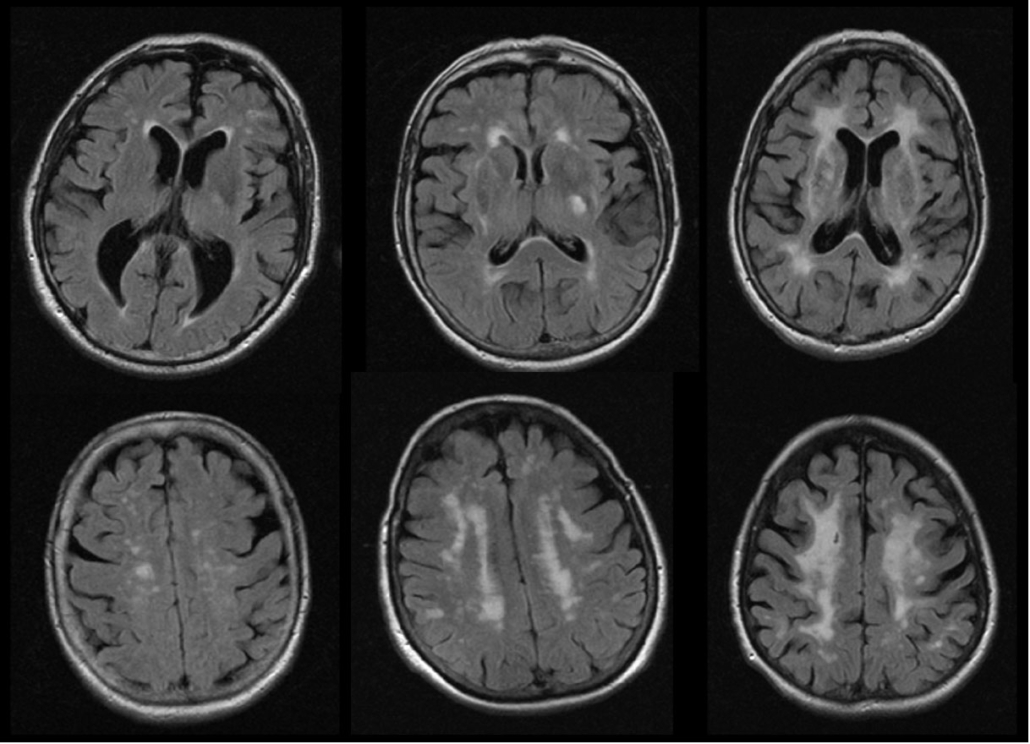

Más allá del ictus entendido como evento clínico reconocible por los mencionados síntomas, es también frecuente la detección de pequeñas lesiones cerebrales vasculares “silentes”, es decir, crónicas, que no han dado síntomas claros jamás, pero que se detectan por casualidad en alguna prueba de imagen cerebral que se indica por algún motivo coyuntural (por ejemplo, para descartar lesiones traumáticas tras un accidente). En este grupo se encuentran los coloquialmente llamados “microinfartos”. Aunque su repercusión suele ser menor a la de un ictus, su acumulación puede producir ciertos problemas, por ejemplo, de memoria, de manejo en la vida diaria o en el trabajo, o de destreza motriz, en las personas que los sufren. Es aquí donde, nuevamente, aclarar su origen y tomar las medidas para detener su aparición resultan claves para evitar la progresión de estos problemas o incluso que finalmente acontezca un ictus en un futuro próximo.